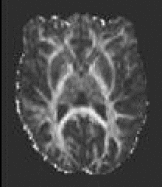

Outputs of bedpostx or dtifit can be conveniently displayed in fslview. If you open an image of diffusion vectors (e.g., dtifit_V1 output of dtifit or dyads<i> output of bedpostx) then it is possible to display these vectors using RGB coding (where the colours red,green and blue represent diffusion in the x,y,z axes respectively) or using lines where a line at each voxel represents the principle diffusion direction at that voxel.

It is also possible to display multiple lines per voxel. Each line will be displayed in a different colour. In the example above, the red lines represent the main fibre orientation, and the blue lines represent the secondary fibre orientations (thresholded at an f-value of 0.05), as calculated by bedpostx.

If you only want to visualise fibres within voxels where multiple fibres are supported (e.g. above a certain threshold for the corresponding mean_f<i>samples), then you first have to create a vector file where the voxels below a certain f-threshold are zeroed. You may use the two following command for that:

maskdyads dyads<i> mean_f<i>samples 0.05

For more details see the relevant fslview tutorial.